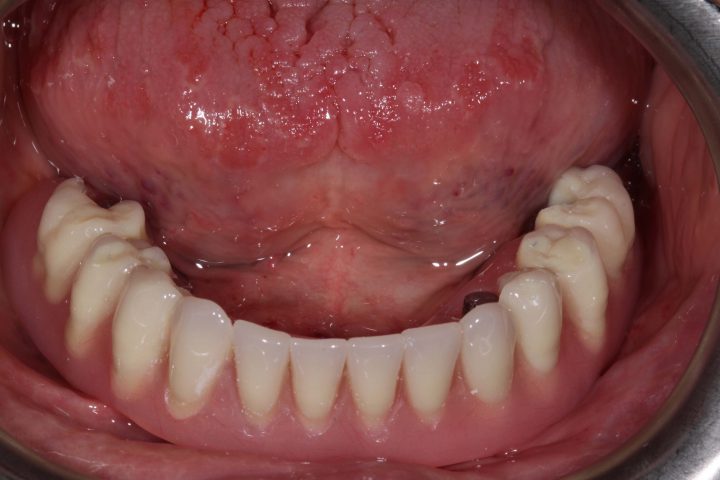

PRIMA

dopo

Arcata superiore - Fase iniziale, intermedia e finale

Caso risolto con Toronto Bridge - Fase iniziale, intermedia e finale